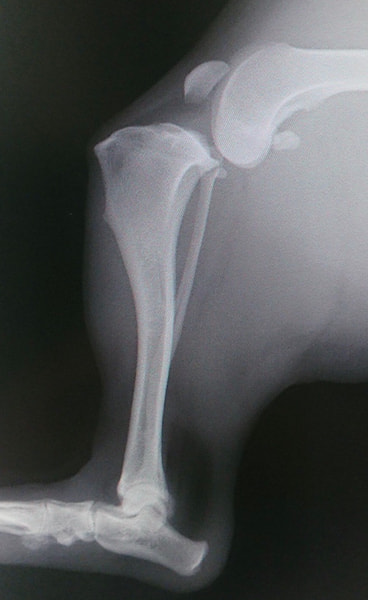

HPの外科の「その他の整形外科疾患」のページに、犬の足根関節の部分関節固定術を追加致しました。(コチラ)足根関節は脛骨、腓骨、踵骨、距骨、足根骨、中足骨と複数の骨で形成され、その関節構造は複雑であり複数の靭帯と腱で安定化されています。足根関節の脱臼や亜脱臼は、主に落下や激しい運動中の外傷によって生じます。症状として、患部は熱感を持って腫れ、動物は痛みにより後肢を挙上したり、負重を避けるように行動します患部g腫れ、動物は痛みにより歩行時や排泄時に体重がかからないように庇。治療法は、軽症の場合は副子や装具による保存療法を行いますが、重症の場合は靭帯修復や関節を固定する関節固定術を行う必要があります。歩行異常や足を庇うような仕草が認められる場合はお早めにご相談下さい。

前十字靱帯断裂症例(2025/02/06)

外科の前十字靱帯断裂のページに、犬のTPLO(脛骨高平部水平化骨切り術)手術を行った症例を追加致しました。大腿骨と脛骨を繋ぐ靱帯の一つである前十字靱帯が断裂すると膝の関節が不安定となり関節炎が進行します。また、膝関節においてクッションの役割を果たしている半月板にもダメージが加わり、痛みを生じて正常な歩行が出来なくなります。治療として多くの場合手術が選択されますが、術後の回復の早さなどから近年ではTPLO法(脛骨の一部を切り角度を調整し膝関節を安定化させる手術)が多く選択されています。

犬のTPLO(脛骨高平部水平化骨切り術)手術(2024/08/07)

外科の前十字靱帯断裂のページに、犬のTPLO(脛骨高平部水平化骨切り術)手術を行った症例を追加致しました。大腿骨と脛骨を繋ぐ靱帯の一つである前十字靱帯は、断裂すると膝の関節が不安定となり関節炎が進行し、またクッションの役割を果たしている半月板にもダメージが加わることで、痛みを生じて正常な歩行が出来なくなります。治療として多くの場合手術が選択されますが、術後の回復の早さなどから近年ではTPLO法(脛骨の一部を切り角度を調整し膝関節を安定化させる手術)が多く選択されています。

前十字靭帯断裂(2024/03/19)